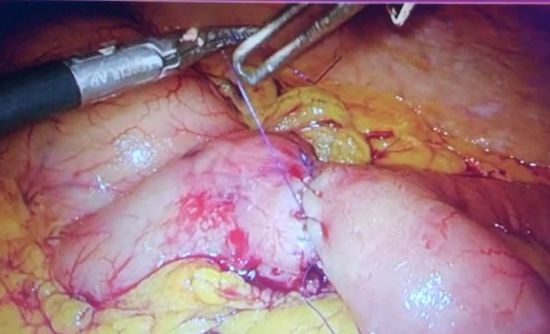

诊断:1.胃癌,性质待病理;病理活检,胃镜病理示:(胃体)粘膜轻度慢性炎,中度萎缩,部分腺体高度异型增生,局部呈腺癌改变。处理:完善辅检后行腹腔镜胃癌根治术,术中注意肝十二指韧带及脾门区血管解剖,这样才不会导致术中操作不当的出血。遵循正确的手术方法。遵循术中清扫步骤,首先要暴露脾门区,其次裸化胃网膜左血管和裸化脾动脉,最后裸化脾叶动脉。处理好术后的并发症。肝十二肠韧带及脾门淋巴结清扫最容易发生的并发症是引起血管的损伤,脾被膜的损伤,引起出血,术中控制不了出血的话只能进行脾切除,本例手术顺利。术后胃肠外营养,抗感染,补液。术后7天治愈出院。